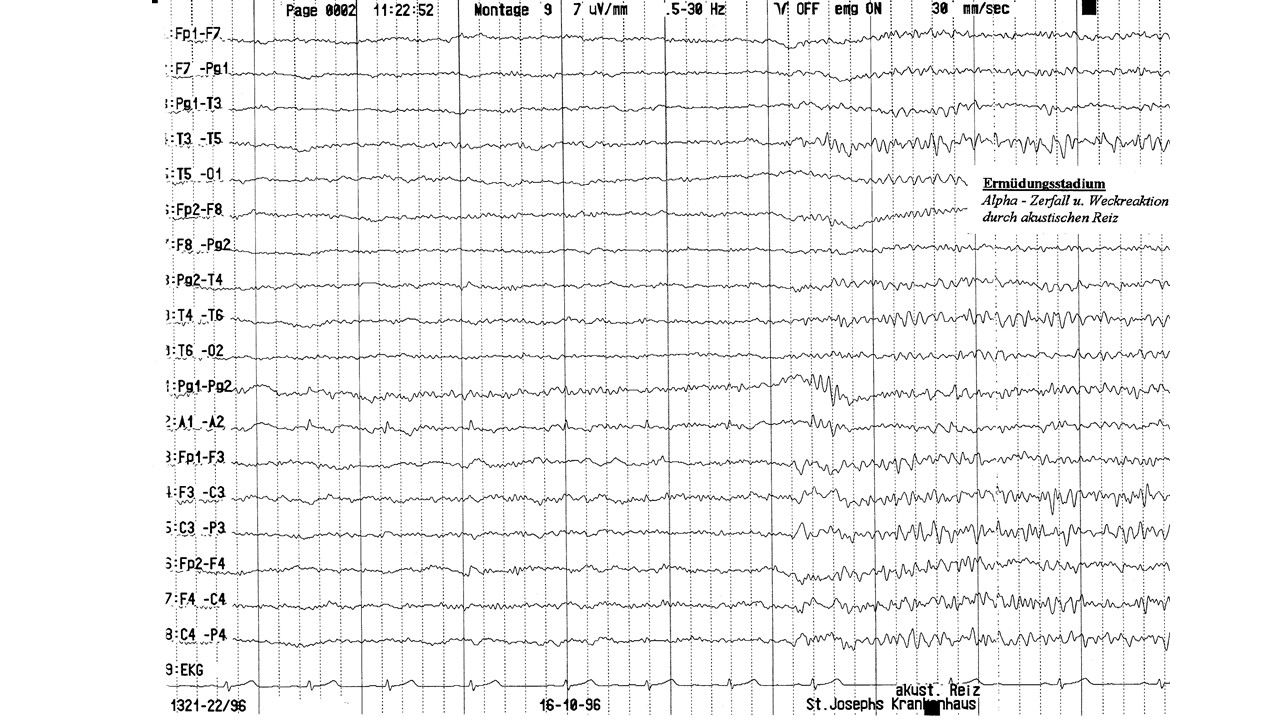

folie616.jpg